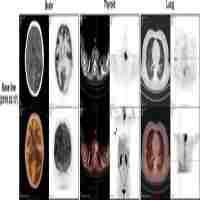

| Abstract | Background: Grade 2/3 meningiomas have locally aggressive behaviors often requiring additional treatment plans after surgical resection. Herein, we explored the clinical significance of next-generation sequencing (NGS) in characterizing the molecular profiles of high-grade meningiomas. Methods: Patients with intracranial meningioma who underwent surgical resection in a single institution were retrospectively reviewed. Clinicopathologic relevance was evaluated using recurrence-free survival (RFS) as an outcome measure. NGS for the targeted gene regions was performed in 40 participants. Results: Among the 713 individuals in the study population, 143 cases (20.1%) were identified as having grade 2 or 3 meningiomas with a significantly lower female predominance. While the difference in RFS between grade 2 and 3 meningiomas was insignificant, a few conventional grade 2 cases, but with TERT promoter hotspot mutation, were highly progressive and refractory to the treatment. From the NGS study, recurrent mutations in TRAF and AKT1 were identified with a higher prevalence (17.5% and 12.5%, respectively) compared with grade 2/3 meningiomas reported in previous literature. However, their relations to other histopathologic properties or clinical factors were rarely observed. Conclusions: Grade 2/3 meningiomas show a broad spectrum of molecular profiles, as they have heterogeneous histologic characteristics. |